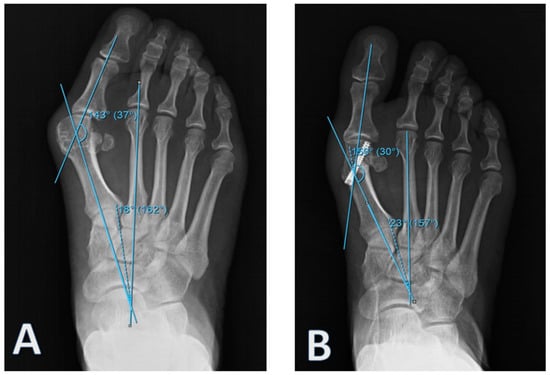

All patients provided informed consent, the study design was approved by the Düzce University Clinical Research Ethics Committee (Düzce, Turkey) (no. 2018/171), and the study was performed in accordance with the principles of the Declaration of Helsinki. This retrospective study includes patients with high to moderate HV, who were above 18 years old, and underwent distal metatarsal osteotomy with the Lindgren–Turan technique between the years 2013 and 2016. A total of 24 patients who were surgically treated were included in this study. Patients diagnosed with hallux valgus with an ache in the first MTP joint, with trouble putting shoes on, with cosmetic complaints, or with sufficient joint range of motion and radiologically over 20 degrees of hallux valgus angle (HVA) and over 10 degrees of intermetatarsal angle (IMA) were included in the study [7] (Figure 1).

Patients with results indicative of osteoarthritis and gout and those who could not adhere to routine clinical follow-ups were not included. Patients in Group 1 to whom the self-locked intramedullary platter was administered were observed for 5 (3–12) months, while patients in Group 2 to whom the Herbert screw was administered were observed for 14 months (8–30). During the postoperative period, short leg splints were administered only to patients in Group 2 for 4 weeks. A total of 18 feet from 12 patients were fixed using an intramedullary platter and another 18 feet from 12 patients were treated using Herbert screw (Figure 2).

Figure 1. An example of (A) preoperative and (B) postoperative radiographic examinations of patients in Group 1.